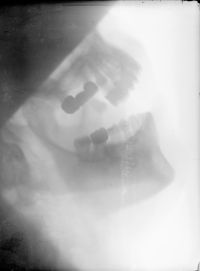

Image[Radiographie montée. Maxillaires supérieur et inférieur de profil, avec appareillage.]